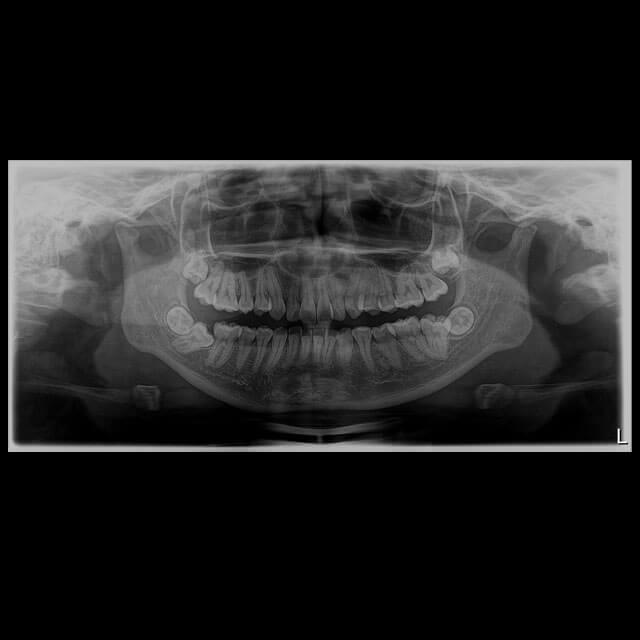

Radio Panorâmica

A radiografia panorâmica é uma ferramenta que permite uma exploração detalhada do complexo dento maxilar. Ou seja, permite obter uma radiografia completa da parte superior e inferior da mandíbula.

São fotografias abrangentes da face e dos dentes. Portanto, oferecem uma visão que seria invisível a olho nu.